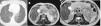

En la tomografía computarizada toracoabdominal se evidenciaba una estenosis de esófago y bronquiectasias de aspecto quístico de predominio en los lóbulos inferiores (LLII), así como una masa retroperitoneal (figs. 1A y B) que se extiende entre las estructuras normales retroperitoneales sin comprimirlas, vasos a su través y adyacentemente adenopatías retrocrurales y retroperitoneales, similar a la masa, recomendándose una resonancia magnética (fig. 1C). Tras presentar el caso en el comité con oncología y cirugía general se decide tratamiento con Rapamune® (sirolimus) 2mg en el desayuno, con excelente tolerancia, y se instaura tratamiento inhalado con vilanterol/furoato de fluticasona 92/22mcg.

A: TC torácica. Bronquiectasias centrales y lobares de predominio en ambos LLII de aspecto quístico en LII con pérdida de volumen asociado. B: RMN de abdomen. Lesión retroperitoneal de al menos 80×95mm (T×L), hiperintensa en pT2 con presencia de tabiques en su interior y zonas con restricción de difusión y captación de contraste que sugieren componente sólido. C: RMN de abdomen. Práctica resolución de la masa quística retroperitoneal, con tamaño actual de unos 12×35×34mm.